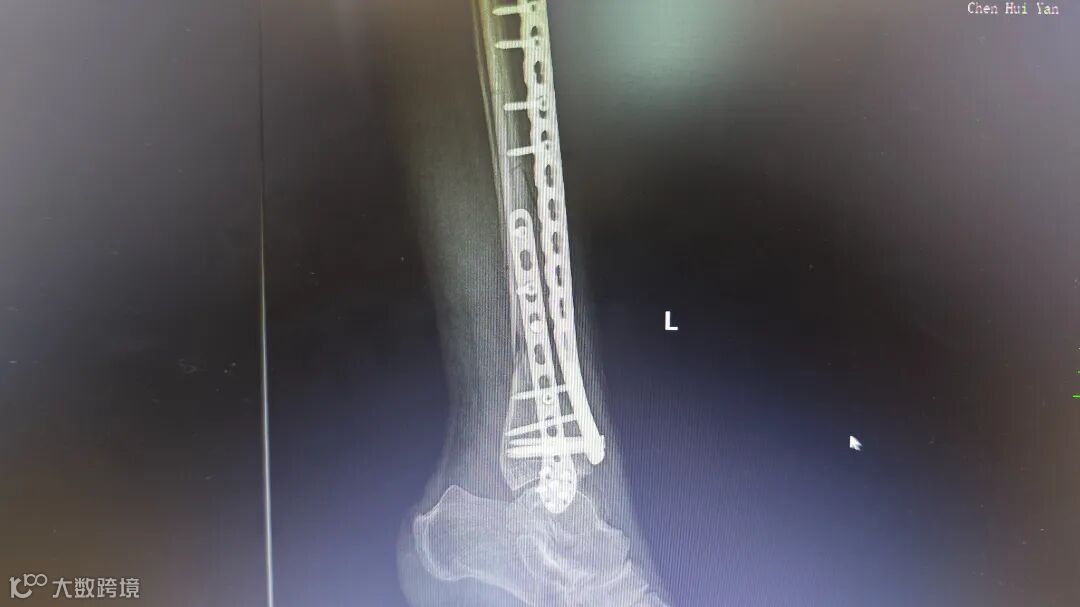

术前腿部影像

胸外科专家会诊后确认,患者肋骨骨折无明显位移,决定采用胸带固定配合卧床静养的保守治疗方案。针对更为复杂的小腿骨折,骨科团队在5月4日由张均锦主刀,曹桂青、陆仕邦医师协助下实施了精准复位手术。术中使用接骨板进行内固定后,X光显示骨折端对位良好,术后第三天患者已能进行简单的足部活动。